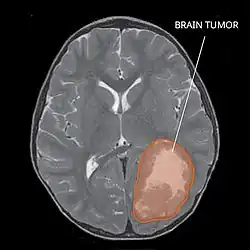

| Primitive neuroectodermal tumor of the central nervous system in a 5-year-old |

A central nervous system primitive neuroectodermal tumor, often abbreviated as PNET, supratentorial PNET, or CNS-PNET,[1] is one of the 3 types of embryonal central nervous system tumors (medulloblastoma, atypical teratoid rhabdoid tumor, and PNET).[2] It is considered an embryonal tumor because it arises from cells partially differentiated or still undifferentiated from birth.[1] Those cells are usually neuroepithelial cells,[1][2][3] stem cells destined to turn into glia or neurons.[4] It can occur anywhere within the spinal cord and cerebrum and can have multiple sites of origins, with a high probability of metastasis through cerebrospinal fluid (CSF).[1][2]

Several analysis can be used to determine the presence of the disease. Physical examinations showing papilledema, visual field defects, cranial nerves palsy, dysphasia, and focal neurological deficits are evidences for possible tumor.[2] PNETs can also be spotted through computed tomography (CT) and magnetic resonance imaging (MRI).[2] In images produced by MRIs, an irregular augmentation among a solid mass will indicated the presence of tumor.[3] However, the results of MRIs are usually ambiguous in defining the presence for this specific tumor.[2] In CT scans, the presence of PNETs will be indicated by an elevated density and an increase in volume of the brain.[2] The CT scan can also show calcification,[3] which is present in 41-44% of PNET cases.[2] Since the tumor can be replicated in other parts of the nervous system through the cerebrospinal fluid (CSF), a CSF analysis can also be conducted.[2] A spinal MRI is a fourth type of analysis that is useful in investigating the level of tumor propagation to the spinal cord.[2]